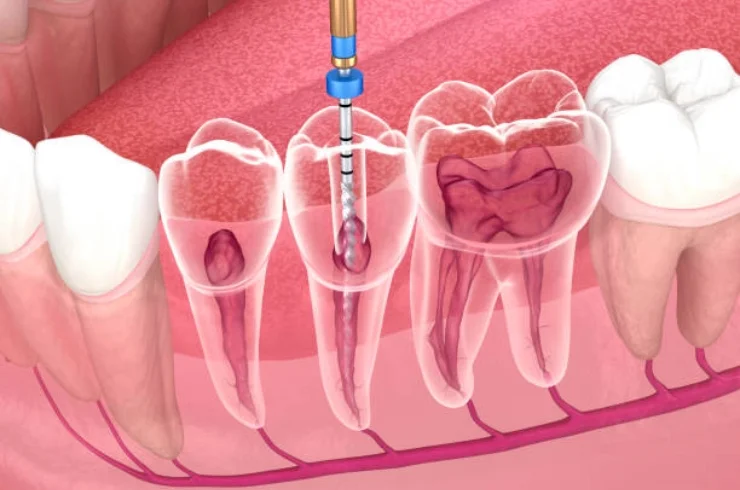

Root Canal Therapy

Root canal therapy saves infected or damaged teeth by removing the infection, relieving pain, and preserving the tooth's structure for long-term oral health.